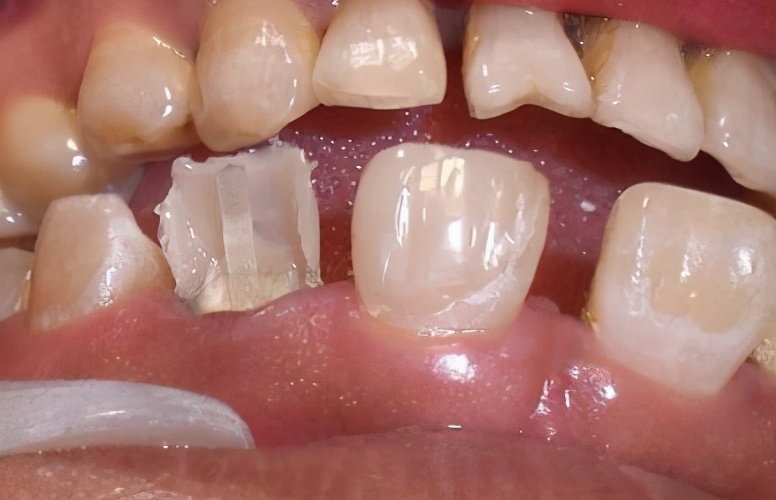

4、牙冠损坏

在某些情况下,会在口腔中多种力量的作用下使得牙冠遭受到损坏,一旦遭受损坏则会逐渐形成裂缝,最终使得牙冠与牙齿之间的密封部位发生了松动,导致牙冠脱落。